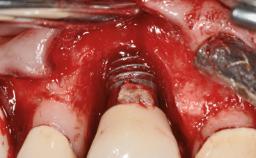

A 27-year-old male was referred to the periodontist for assessment and management of implant site 41. The implant had been placed nine years previously and restored with a screw-retained single crown. The patient was a cigarette smoker in good general health. He reported he had reduced his smoking habit from 25 cigarettes per day to 15 cigarettes per day in the previous six months. On examination, there was calculus and plaque present at the lower anterior teeth and at implant site 41. Localized attachment loss was observed at teeth 32 and 42, with 2–3 mm of gingival recession. At implant site 41, there were 8–9 mm probing depths with suppuration and bleeding on probing.